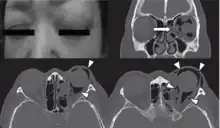

Woman with preorbital swelling in orbital emphysema shown in CT scans

Orbital emphysema (/ˈɔː(r)bɪt(ə)l ˌemfɪˈsiːmə/, also known as pneumo-orbit[8]) is a medical condition that refers to the trapping of air within the loose subcutaneous around the orbit that is generally characterized by sudden onset swelling and bruising at the impacted eye, with or without deterioration of vision, which the severity depends on the density of air trapped under the orbital soft tissue spaces.[1][9]